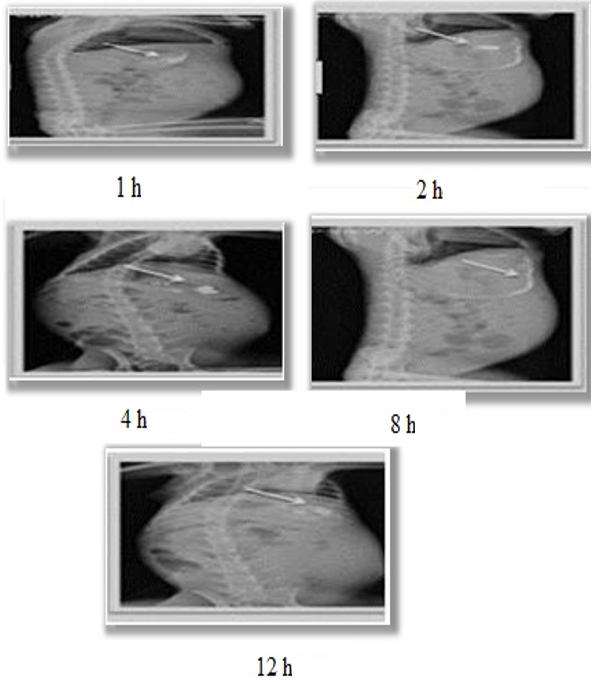

Barium Sulphate helps to uncover dosage form in the GIT by which one can predict and correlate the gastric emptying time and the passage of dosage form. In gastro-scope and ultrasonography studies can be included in the in vivo evaluation of gastroretentive drug delivery systems [28]. The scintigraphs showed that all the formulations were intact in the physiological environment of stomach as depicted in fig. 2. Gamma scintigraphy study was performed to evaluate qualitative gastro retention following oral administration of barium sulphate formulations and to support quantitative pharmacokinetic outcomes. The images were captured at 1, 2, 4, 8 and 12 h post-administration. The rabbits showed an accumulation of microspheres at 1 h, which reached to maximum at 24 h showing prominent retention in gastric environment [29].

Fig. 2: Scintigraphy of floating microspheres

To determine the in vivo gastroretentive study after oral administration of formulation, imaging analysis is one of the most reliable and accurate tools. Gamma scintigraphy study is one such non-invasive imaging analysis technique [18]. It was performed after approval of protocol by the Institutional Animal Ethics Committee (1687/PO/Re/S/2021/CPCSEA). The in vivo radiographic studies were conducted in healthy male Albino rabbits (Vab bioscience, Hyd.) of 2 to 3 kg weight brought and kept to acclimatize for normal day and night cycles for 10 d. During this period they were given with standard diet, rabbits were divided into two groups (group 1 and group 2). Three rabbits were selected for each group to give Barium sulphate-loaded microspheres suspension and formulated floatingtabletin order to examine the floating behavior [18]. Rabbit were fasted for 12 h prior to the study and the dose equivalent of 70 mg of microspheres were given to the rabbit in the form of suspension followed by giving sufficient amount of drinking water. The location of the formulation was identified by gamma scintigraphy by restricting the movement of the animal; they were not allowed to take food until the entire experiment was completed [19].